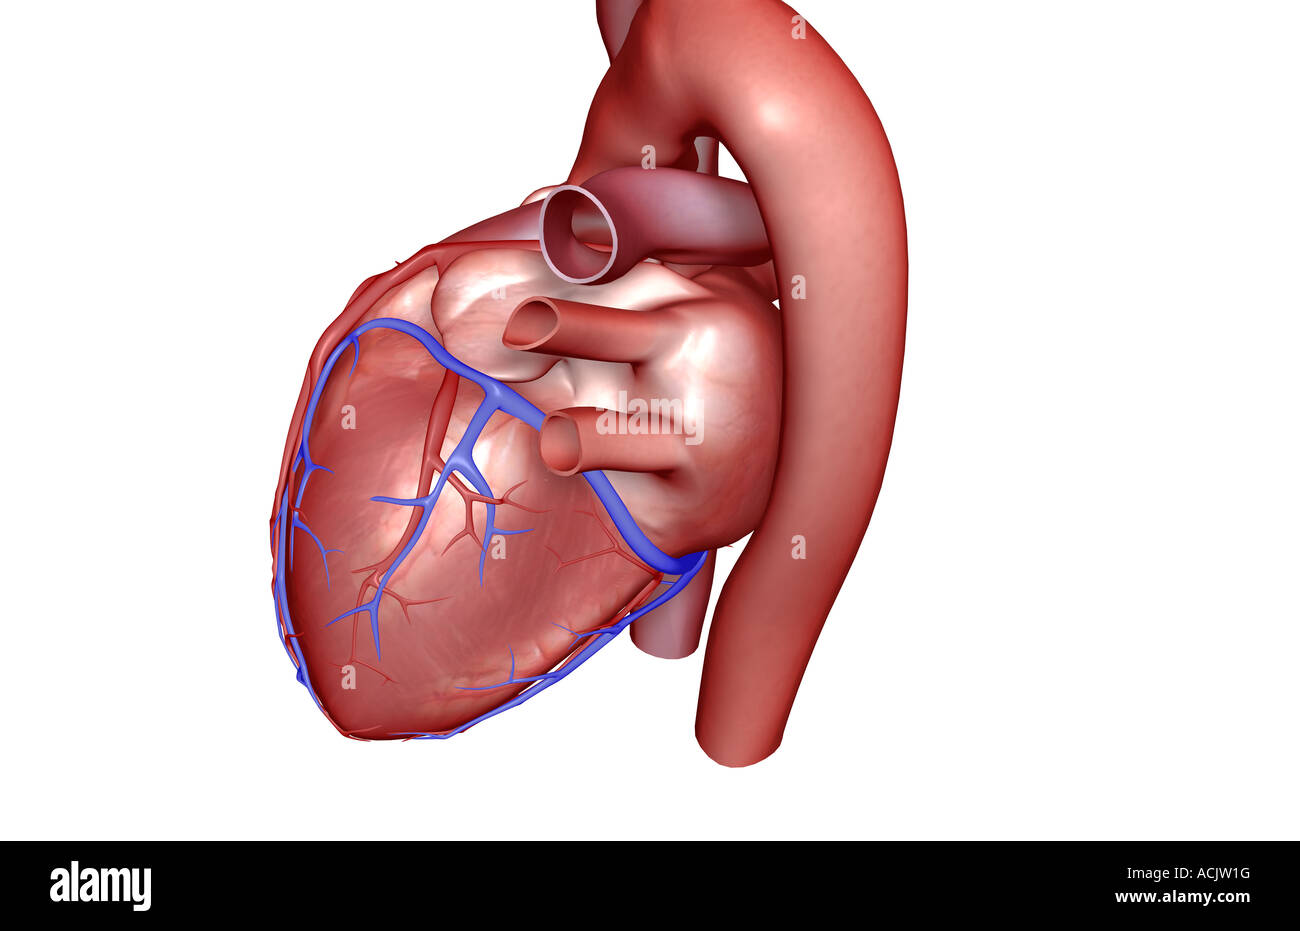

The coronary vessels of the heart Stock Photohttps://www.alamy.com/image-license-details/?v=1https://www.alamy.com/stock-photo-the-coronary-vessels-of-the-heart-13173339.html

The coronary vessels of the heart Stock Photohttps://www.alamy.com/image-license-details/?v=1https://www.alamy.com/stock-photo-the-coronary-vessels-of-the-heart-13173339.htmlRFACJW1G–The coronary vessels of the heart